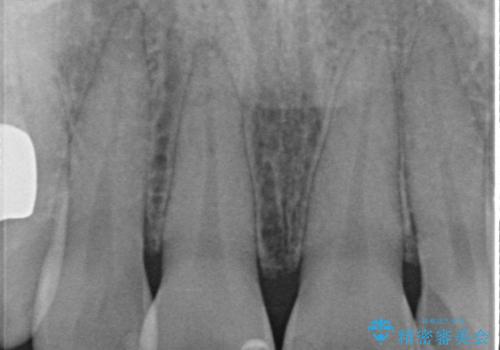

前歯に変色が起こる場合、神経組織の失活により引き起こる可能性が高いため、診察を行ったところ、根尖部の病変や叩いたときの痛みなどが認められました。

まずは根管治療を行い、痛みの消退を確認してからオールセラミッククラウンによる補綴治療を行うこととしました。

前歯に痛みがあるという実感はなかったそうですが、診察で叩いたときの痛みを感じた際、今までに同様の痛みや違和感を感じたことがあったとのことでした。

初回の根管治療で痛みや違和感は消退したため、その後は速やかに補綴治療を行いました。